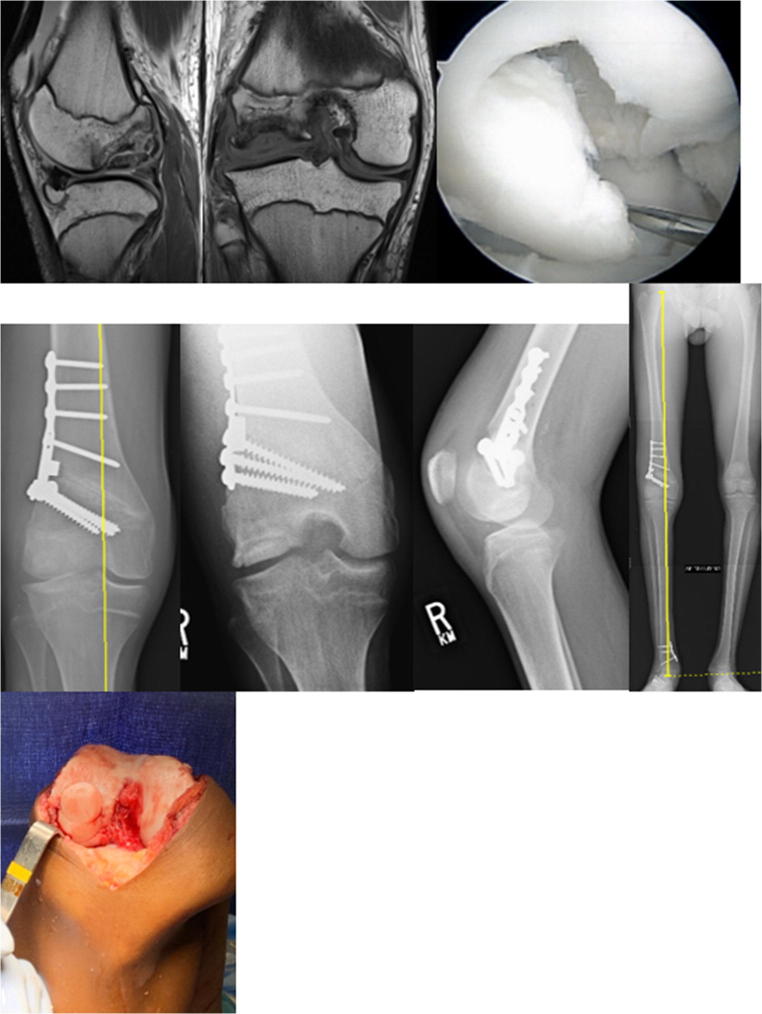

In skeletally mature adolescents with coronal malalignment and an OCD requiring salvage treatment, alignment correction can be corrected with a distal femoral or proximal tibial osteotomy, with the goal of unloading the affected compartment and protecting the salvage surgery. The authors’ ideal correction of the mechanical alignment is to the base of the medial tibial spine for a lateral femoral condyle OCD (Fig. 3) and to the base of the lateral tibial spine for a medial femoral condyle OCD. This corresponds to the Fujisawa point, which is 62.5% of the medial-lateral width of the knee, which effectively unloads the affected compartment [31]. Osteotomy is typically performed at the time of final articular cartilage restoration such as osteochondral allograft transplantation or autologous chondrocyte implantation to limit the patient to one instead of two periods of prolonged altered weight-bearing.

Fig. 3.

16-year-old male with unsalvageable lateral femoral condyle OCD and genu valgum treated with osteochondral allograft transplantation and distal femoral osteotomy